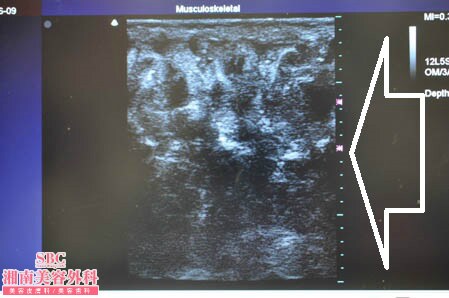

いつものように3Dタッチビュー(超音波)で

皮下脂肪の状態も把握しておきましょう。